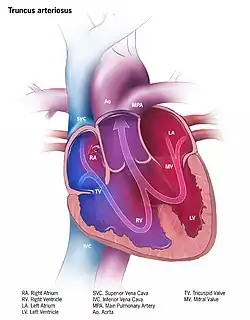

| Illustration of truncus arteriosus | |

Persistent truncus arteriosus (PTA),[1] often referred to simply as truncus arteriosus,[2] is a rare form of congenital heart disease that presents at birth. In this condition, the embryological structure known as the truncus arteriosus fails to properly divide into the pulmonary trunk and aorta. This results in one arterial trunk arising from the heart and providing mixed blood to the coronary arteries, pulmonary arteries, and systemic circulation.[3] For the International Classification of Diseases (ICD-11), the International Paediatric and Congenital Cardiac Code (IPCCC) was developed to standardize the nomenclature of congenital heart disease. Under this system, English is now the official language, and persistent truncus arteriosus should properly be termed common arterial trunk.[2]

Anatomical changes associated with this disorder includes:

- single artery arising from the two ventricles which gives rise to both the aortic and pulmonary vessels

- abnormal truncal valve

- right sided aortic arch in about 30% of cases (not shown)

- large ventricular septal defect

- pulmonary hypertension

- complete mixing occurring at level of the great vessel

- right-to-left shunting of blood